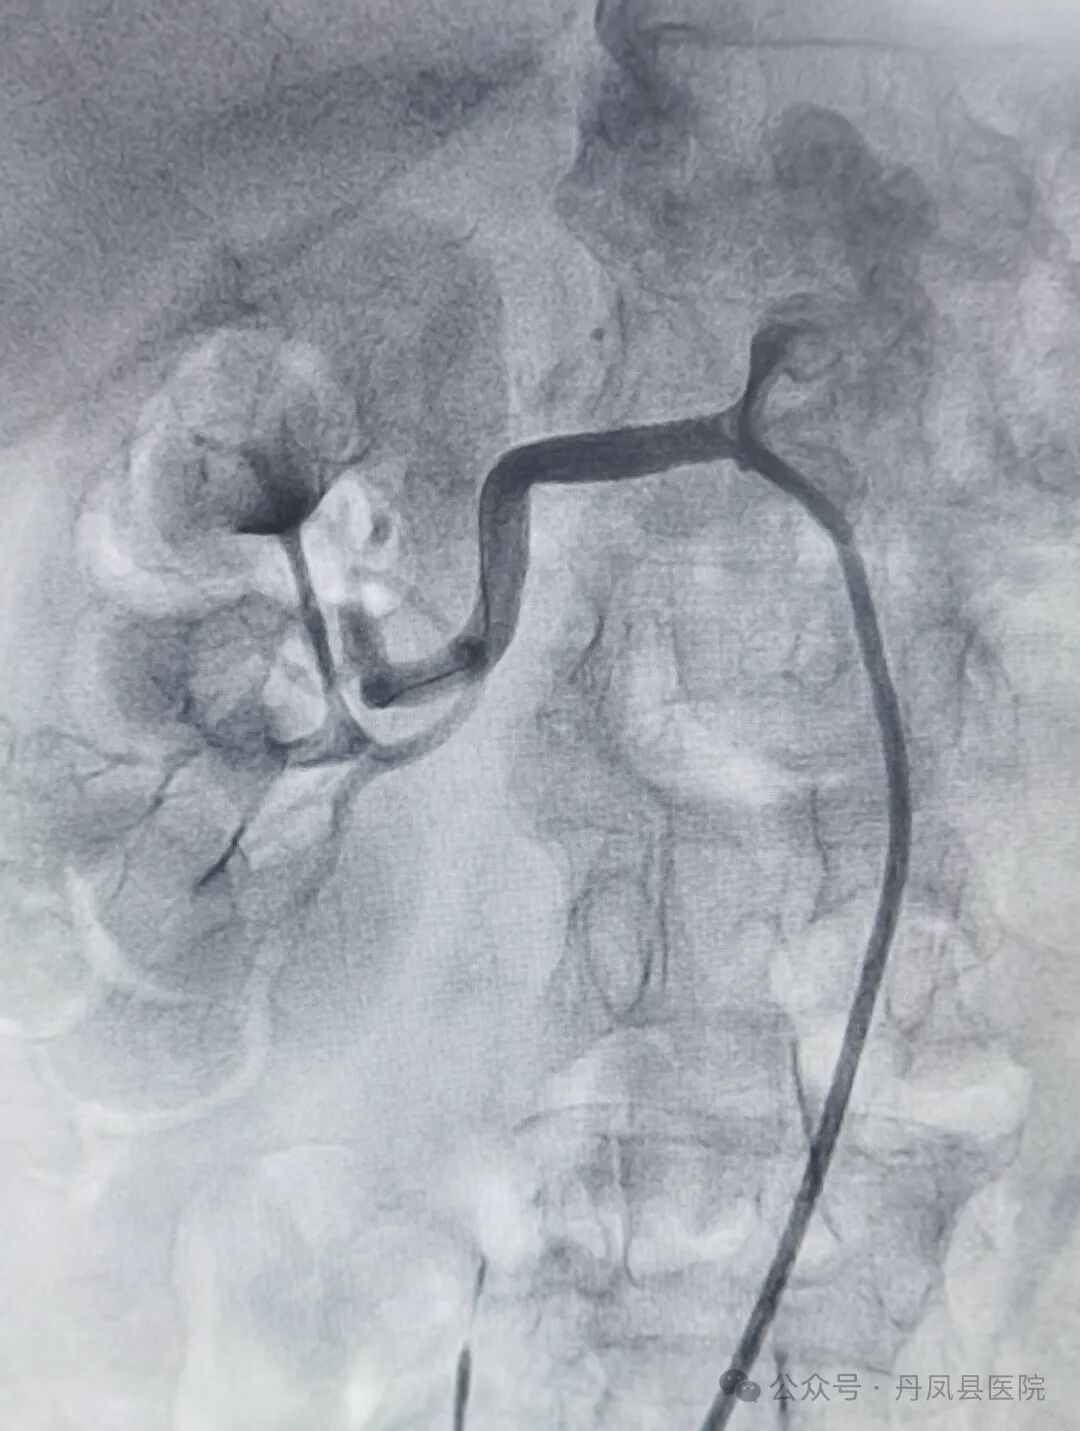

图为术前右肾动脉起始段90%狭窄![]()

图为术后肾动脉狭窄恢复正常【技术亮点】肾动脉支架植入术作为外周血管介入领域的一项重要技术,对于治疗肾动脉狭窄引起的高血压、肾功能损害等疾病具有显著疗效。它通过微创的方式解决了传统手术创伤大、恢复慢的问题,为患者提供了更加安全、有效的治疗选择。此次手术的成功开展,不仅填补了我县在该领域的医疗空白,更为广大肾病及高血压患者带来了新的希望。